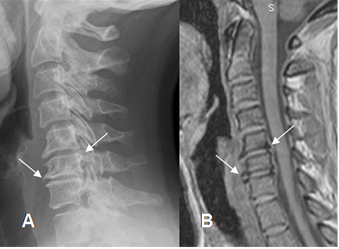

Fig 12. Artropatía degenerativa en columna.

A: Rx lateral y B: RM gradiente eco (GE) sagital, de la columna cervical. Presencia de osteofitos anteriores y posteriores, muy bien definidos en el GE, que es la secuencia de elección para su detección.